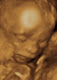

I've been hospitalised 3 times in the last 4-5 weeks with Hyperemesis and severe dehydration that had me constantly fainting and unable to drink or eat anything for days, from the Pregnancy. It has been so difficult on all of us and I cant ever do this again... but it is so wonderful when I get to see the little one within my belly doing so well. Still only at the beginning though.. and praying for relief.. soon! I have felt so disheartened at times.. and often overwhelmed with a deep sense of fear of the things yet to come. How am I going to cope? How is my little boy going to cope? He is finding it so difficult to suddenly lose his mummy (as I can barely show him any attention.. im in bed the majority of the time and have just come out of hospital after another 5day stay).

12wks and 5dys pregnant.